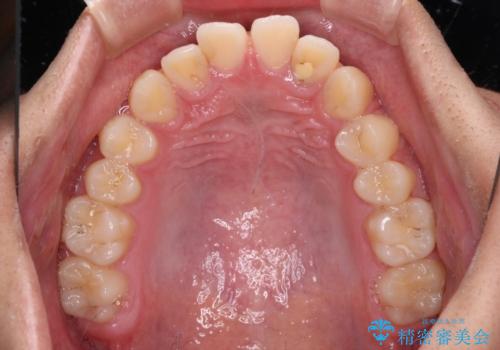

- 前歯のデコボコと隙間を気にして来院された高校生の患者様です。

下顎前歯が上顎前歯を突き上げるような咬み合わせとなっており、その影響で上顎正中に隙間ができている状態でした。

叢生の程度は軽度であり、本人もしっかりと使用する自信があるとのことだったので、インビザラインによる矯正治療を行うこととしました。

突き上げによる隙間を予防する為に、深い咬み合わせを改善するような治療計画としました。咬み合わせを改善させることはできましたが、隙間は後戻りしやすいので、通常の下顎前歯のみではなく、上顎前歯2本もワイヤーで保定を行いました。